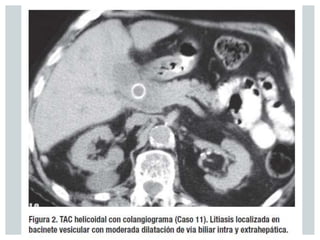

 La tomografía computarizada abdominal puede

mostrar una cavidad irregular cerca del cuello de la

vesícula biliar y cálculos afuera del viscus

 Los hallazgos en la colangiografía sugerentes de SM

son la compresión extrínseca curvilínea o

estrechez, usualmente comprometiendo la porción

lateral del conducto hepático común en su porción

distal con dilatación proximal.